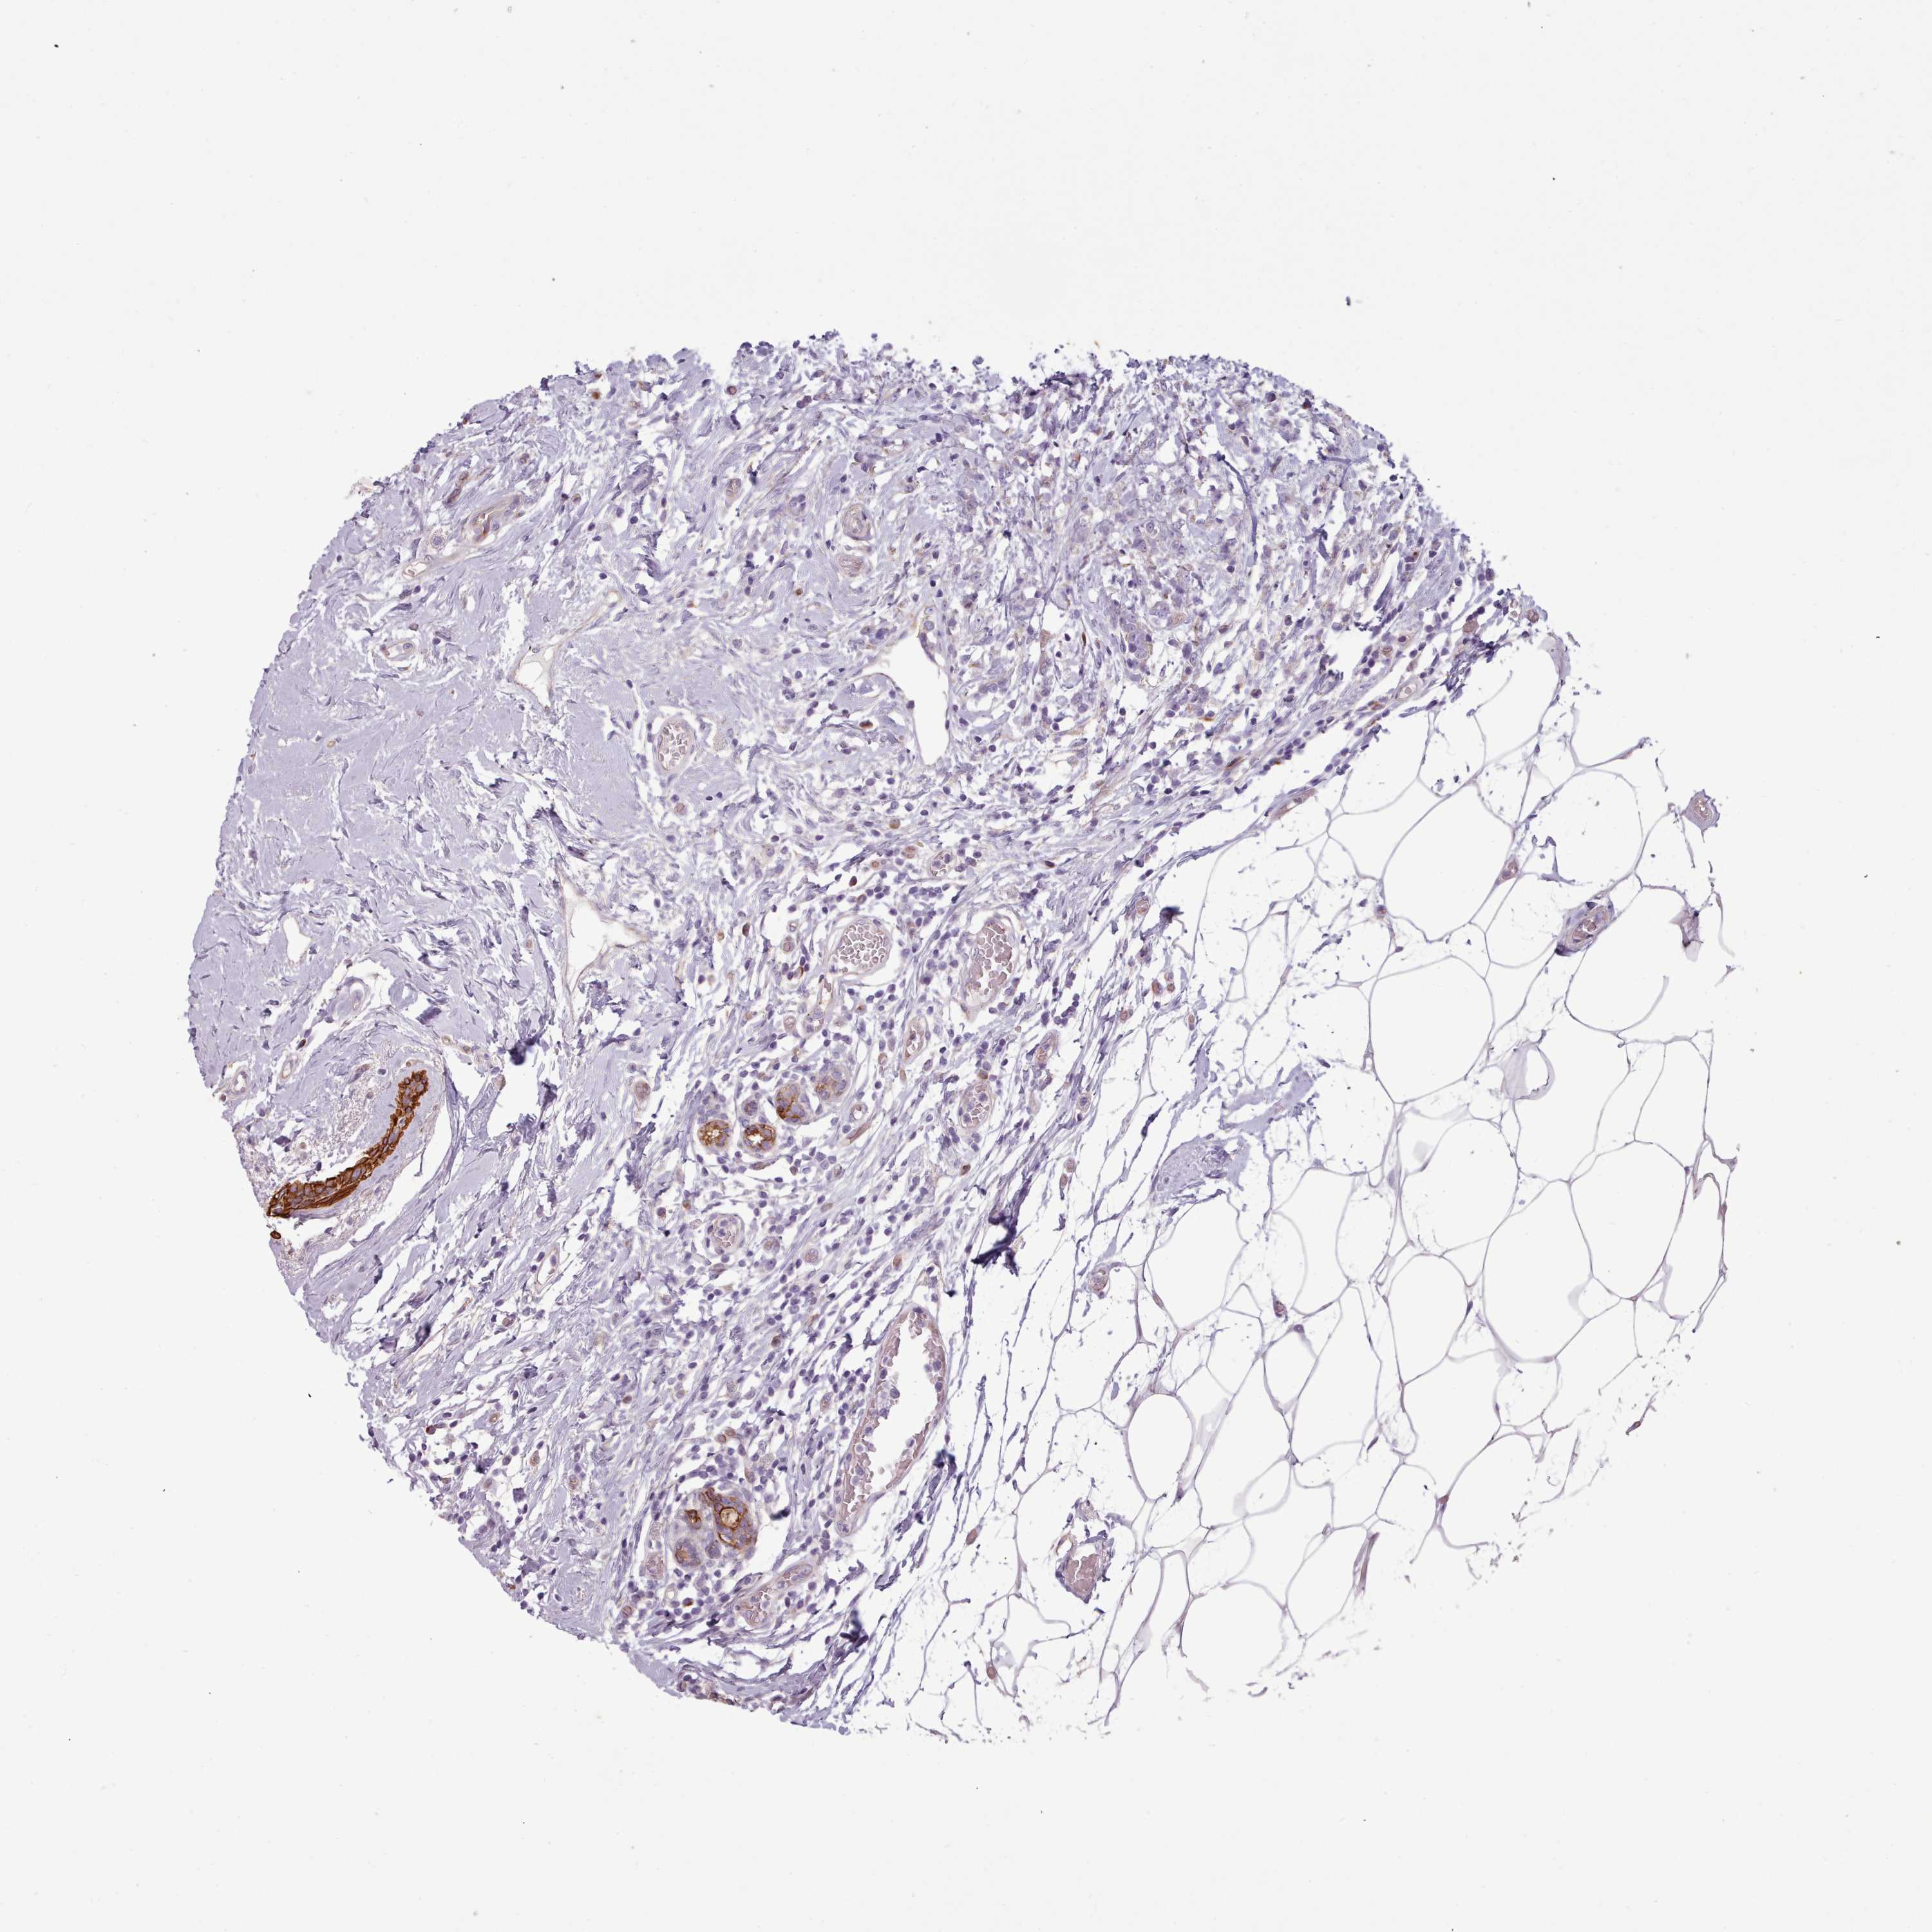

BRCA TCGA BRCA VALIDATION PROTEIN EXPRESSION

ANTIBODIES

AND

VALIDATION